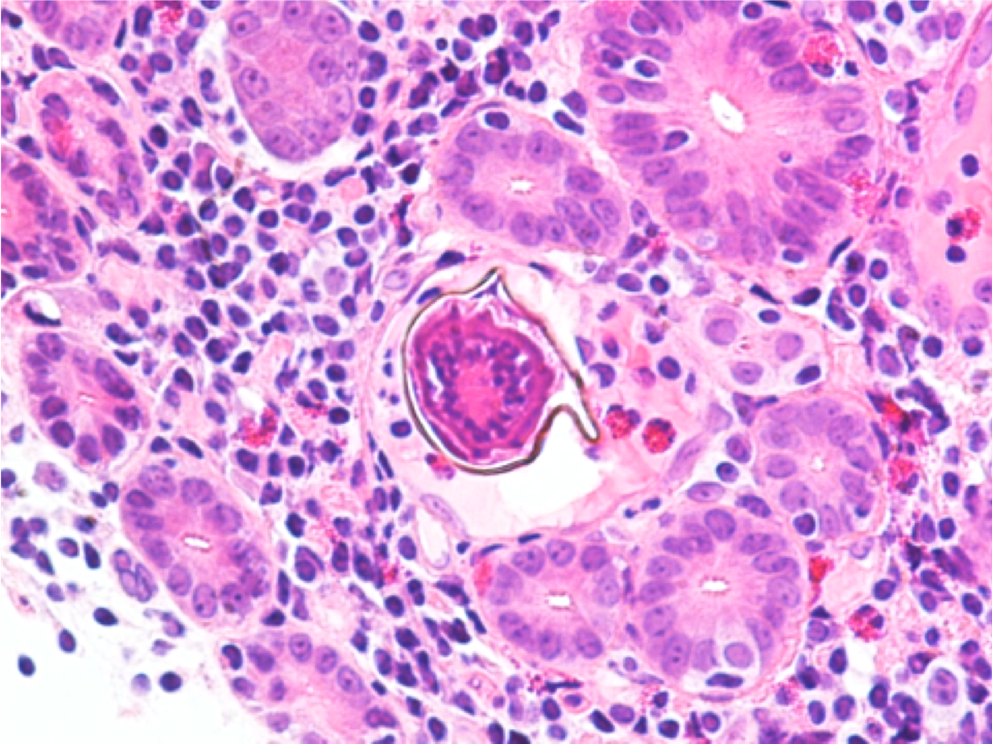

Malaria should be suspected when a patient presents with a febrile illness and a travel history within a malaria-endemic region. Diagnosis of P vivax can be made through microscopic examination of blood smears, immunochromatographic rapid diagnostic tests (RDTs) and nucleic acid detection through amplification techniques.1 Examination of a thick blood smear allows efficient screening for malaria parasites, while a thin blood smear allows for species identification since parasite morphology is more clearly visualized.2 Upon examination of thin blood smears, infections by P. vivax and P. ovale may appear indistinguishable as both species infect immature, enlarged erythrocytes (1.25-2x normal), can be visualized at any stage in peripheral blood (ring, trophozoite, schizont, and gametocyte) and because Schuffner’s dots are a common morphologic feature during most stages. Defining characteristics of P. vivax include the presence of a large, ameboid trophozoite cytoplasm, and fine Schuffner’s dots and schizonts with >12 merozoites. Of note, preparation with Giemsa stain over Wright stain is preferred for demonstration of Schuffner’s dots.2 Immunochromatographic RDTs detect parasite-specific antigens (e.g., Plasmodium lactate dehydrogenase, Plasmodium specific aldolase) in a finger-prick blood sample. These tests are commercially available and relatively simple to perform and interpret, making them a useful tool for resource-limited regions.1 Nucleic acid amplification-based tools (e.g., PCR, loop-mediated isothermal amplification) are not routinely used for clinical management of malaria but do have diagnostic advantages over light microscopy and RDTs.3 PCRs are highly sensitive, can detect mixed infections even at low parasite densities, and are useful for epidemiological studies such as drug resistance identification.1